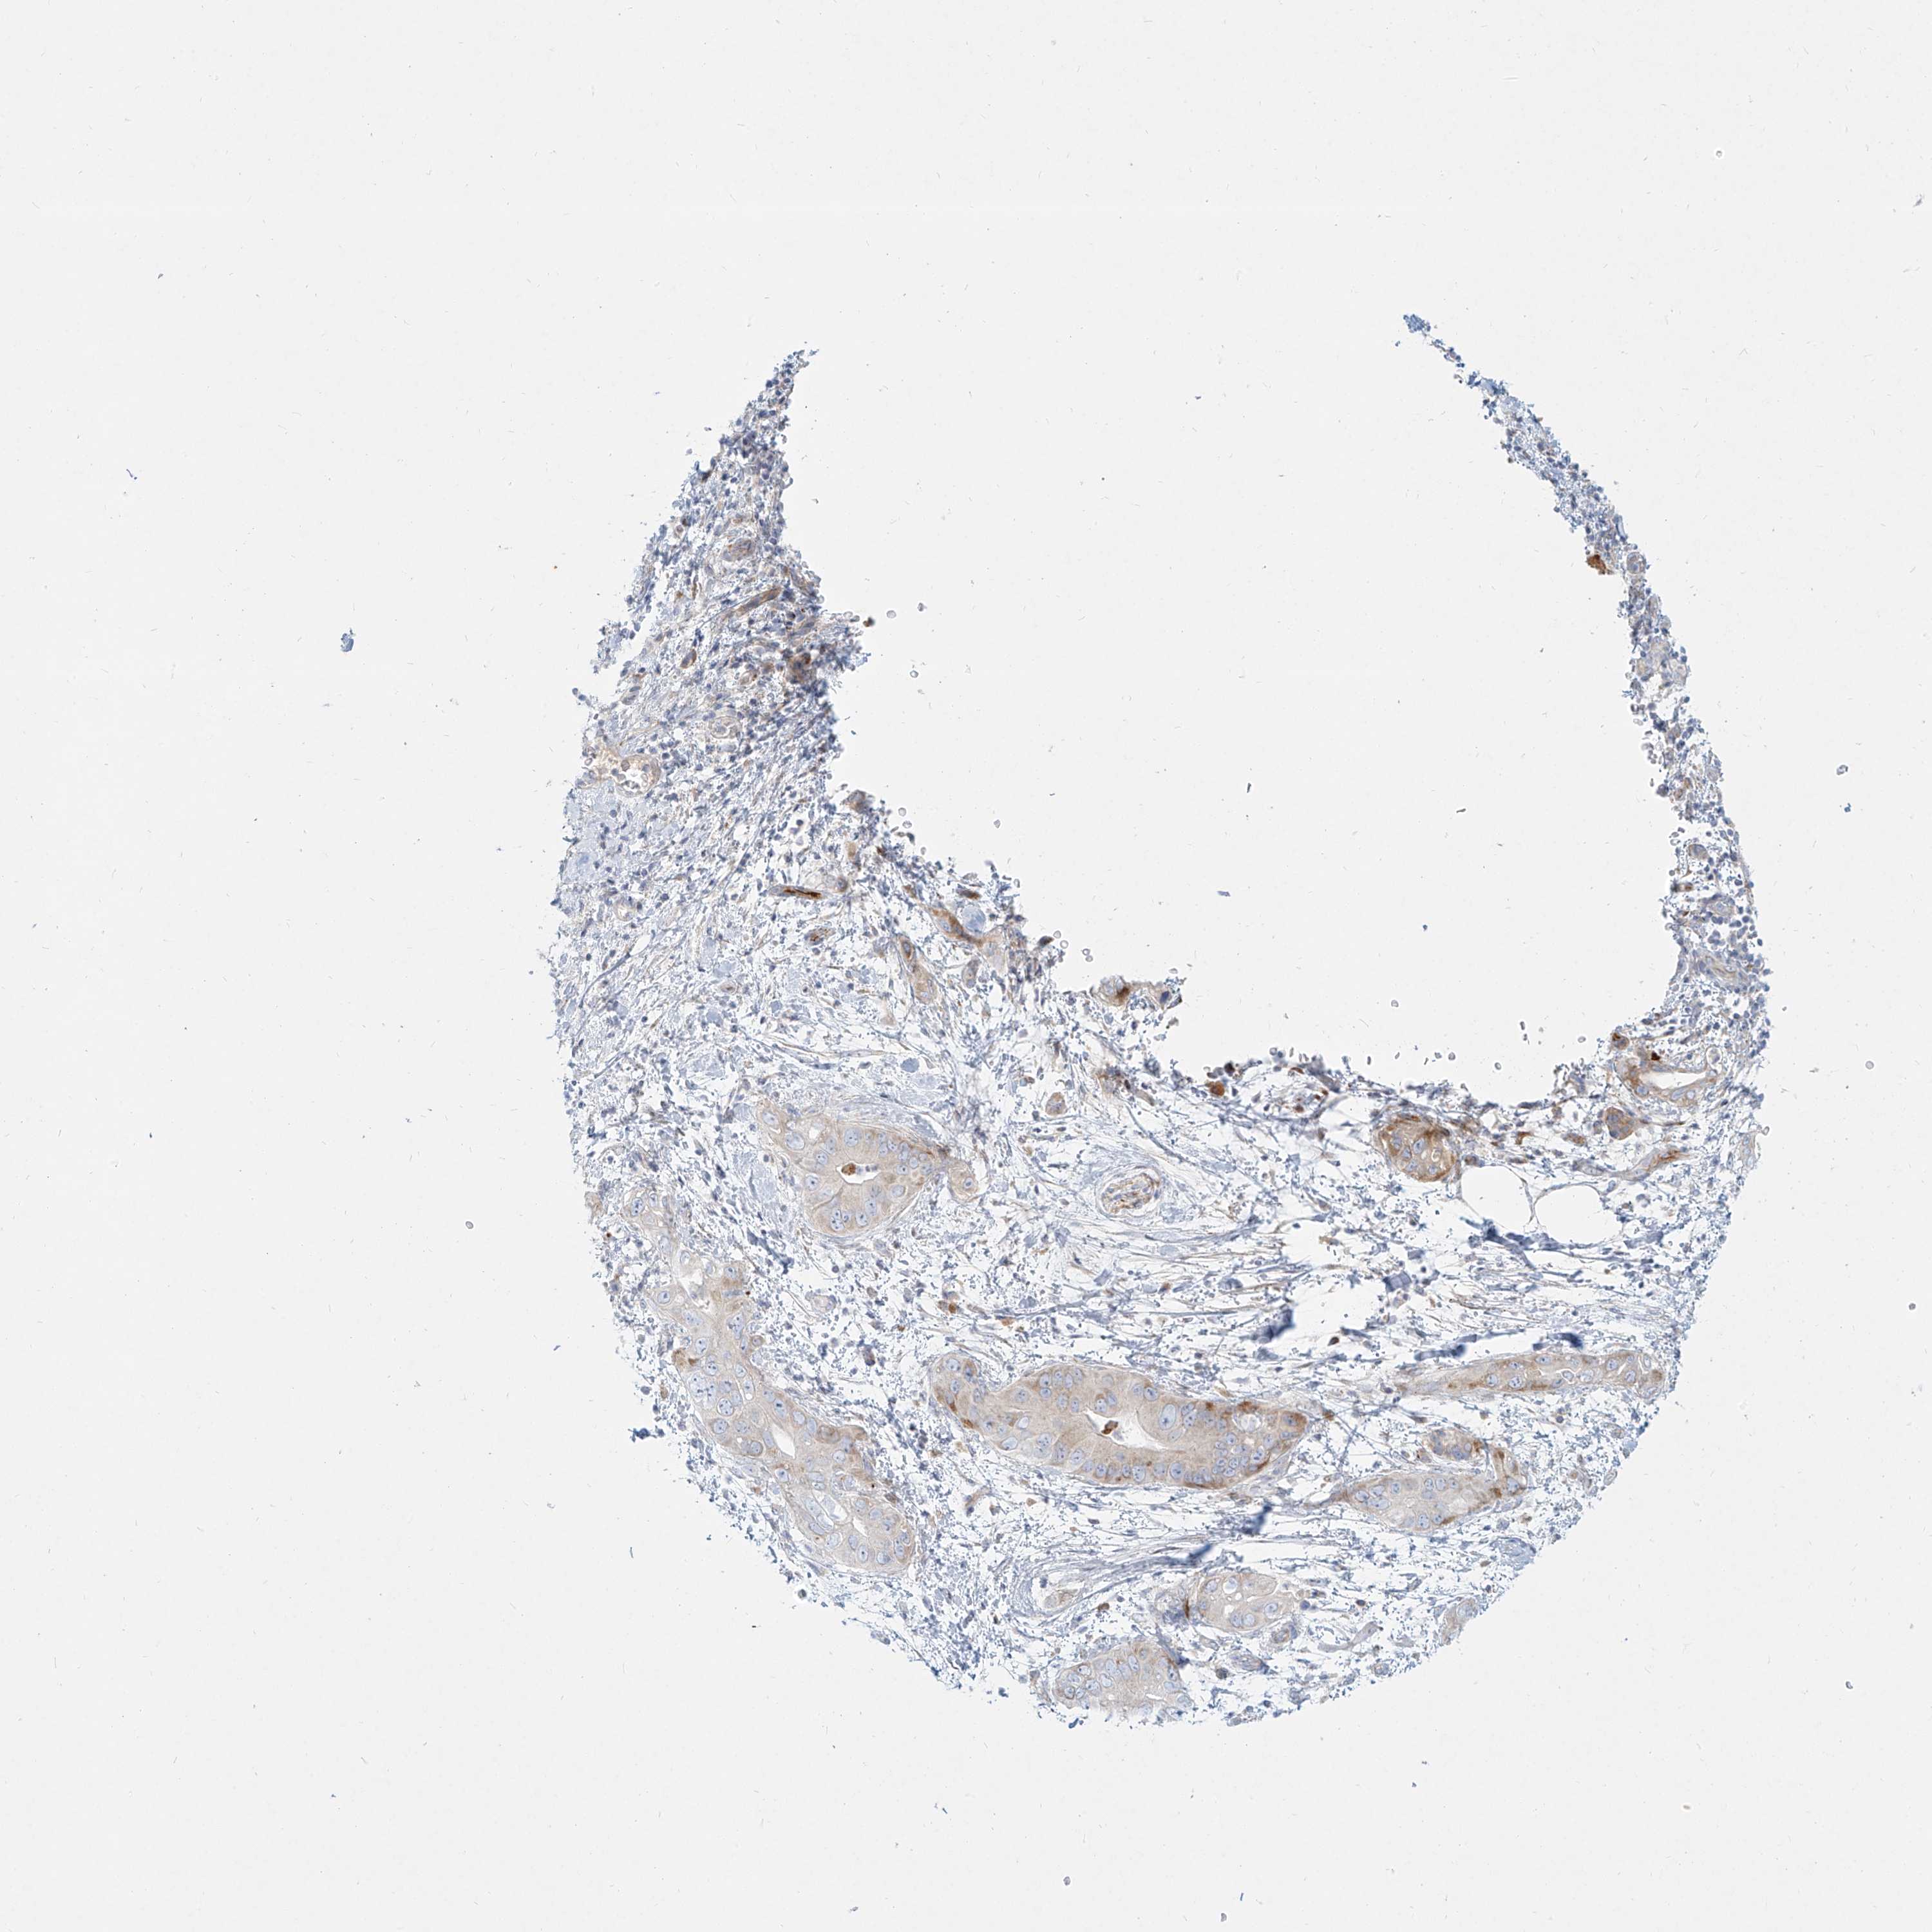

PANCREATIC CANCER - Protein expressioni

A mouse-over function shows sample information and annotation data. Click on an image to view it in a full screen mode. Samples can be filtered based on level of antibody staining by selecting one or several of the following categories: high, medium, low and not detected. The assay and annotation is described here.

Note that samples used for immunohistochemistry by the Human Protein Atlas do not correspond to samples in the TCGA dataset.

Antibody stainingi

Antibody staining in the annotated cell types in the current human tissue is reported as not detected, low, medium, or high, based on conventional immunohistochemistry profiling in selected tissues. This score is based on the combination of the staining intensity and fraction of stained cells.

Each image is clickable and will lead to virtual microscopy that enables deeper exploration of all samples and also displays staining intensity scores, fraction scores and subcellular localization as well as patient and tissue information for each sample.

Antibody HPA031550

Antibody HPA031551

Antibody HPA031552

Staining

High

Medium

Low

Not detected

Intensity

Strong

Moderate

Weak

Negative

Quantity

>75%

75%-25%

<25%

None

Location

Nuclear

Cytoplasmic/membranous

Cytoplasmic/membranous,nuclear

Adenocarcinoma, NOS